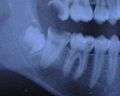

ചിലരിൽ മോണയിൽ കീറലുണ്ടാക്കിക്കൊടുത്താൽ വിവേകദന്തങ്ങൾ കുഴപ്പമില്ലാതെ വളർന്നു വന്നുകൊള്ളും. മുൻകൂട്ടി എക്സ്റേ എടുത്ത് നോക്കിയാൽ ഈ പല്ലുകൾക്ക് പുറത്ത് വരാൻ സ്ഥലമുണ്ടോ എന്നു അറിയാനാകും. മോണയിൽ അല്ലെങ്കിൽ എല്ലിൽ കുടുങ്ങി പോകുക, വീക്കവും വേദനയും ഉണ്ടാവുക എന്നീ പ്രശ്നങ്ങൾ ഉണ്ടെങ്കിൽ ശസ്ത്രക്രിയ മൂലം നീക്കം ചെയേണ്ടി വരും. മേൽവരിയിലെ വിവേകദന്തങ്ങൾ നീക്കം ചെയ്യുന്നത് താരതമ്യേന എളുപ്പമാണ്. വിവേകദന്തങ്ങൾ പ്രശ്നമില്ലാതെ വളരുന്നവരും ശ്രദ്ധിക്കേണ്ടതുണ്ടു. ഭക്ഷണാവശിഷ്ടങ്ങൾ അടിഞ്ഞുകൂടി അണുബാധ വരാൻ സാദ്ധ്യത ഏറെയാണ്.